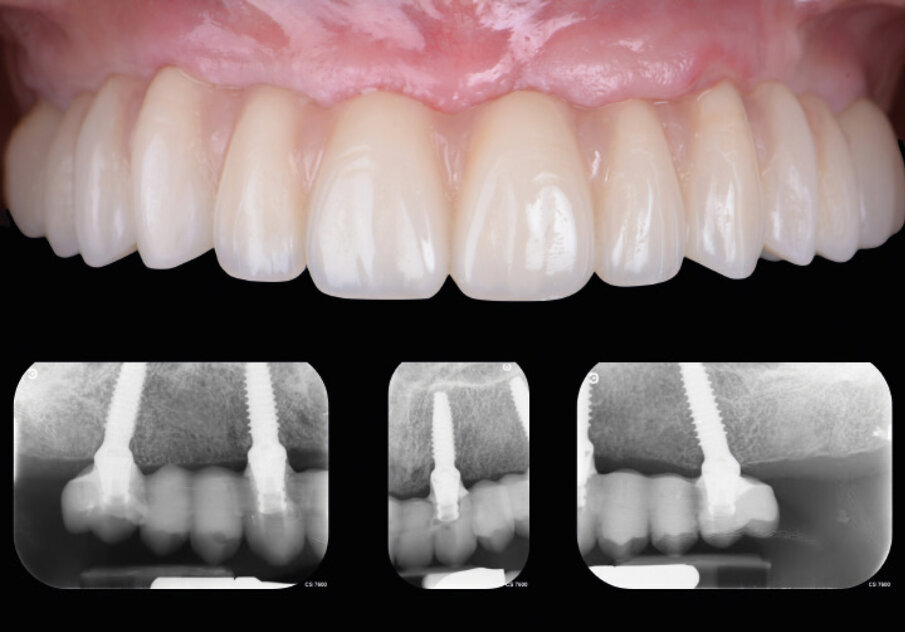

Nella fase di controllo finale possiamo apprezzare come i rapporti di intercuspidazione programmati siano stati perfettamente rispettati (Fig. 28), senza necessità di ricorrere a procedure di auto-centratura della protesi, grazie ad una attenta pianificazione digitale. Eseguiamo una scansione con scan abutment in posizione prima di procedere con la rimozione della dima base e il fissaggio della protesi (Figg. 29-31). Controlliamo le possibilità di mantenimento igienico tenendo conto che, trattandosi di un intervento flapless, non abbiamo le problematiche legate alla gestione di una linea di incisione (Fig. 32). La Fig. 33 mostra la corretta guarigione dei tessuti quindici giorni dopo il trattamento. Eseguiamo un controllo radiografico mirato a verificare il corretto alloggiamento di tutti gli impianti e della protesi (Fig. 33), dove possiamo vedere la struttura di rinforzo in fibra di vetro.

Fig. 33